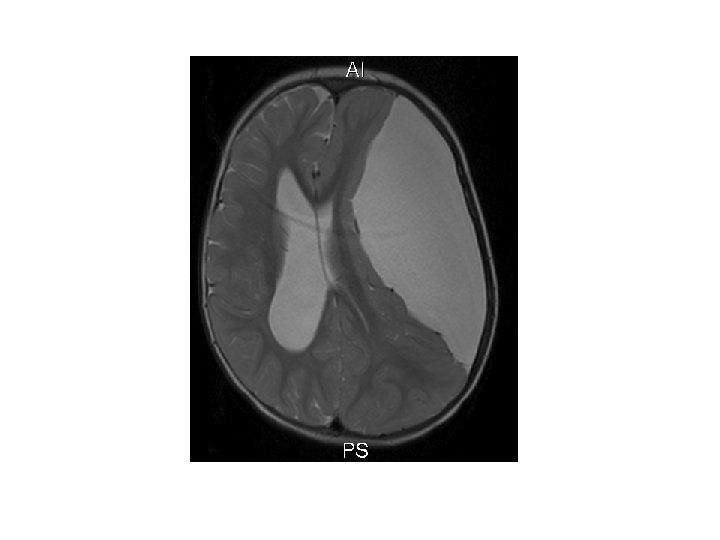

Greining • CT • MRI • Ísótóparannsóknir • Einkennalaust: Greinist oft fyrir tilviljun með CT eða MRI • Einkenni: Gullstandard MRI

Heilaskúmsbelgir - Arachnoid cysts • Skilgreining: – Heila- og mænuvökvafylltir belgir, þaktir heilaskúmsfrumum og kollageni, sem geta myndast á yfirborði heilans, innan heilans eða í mænunni.

Einkenni • Flestir einkennalausir • Breytileg eftir stærð og staðsetningu – – – – – Aflögun á höfði eða aukið höfuðummál Hydrocephalus Aukinn intracranial þrýstingur Höfuðverkur Þroskafrávik Krampar Hegðunarbreytingar Hemiparesa Ataxia O. fl.